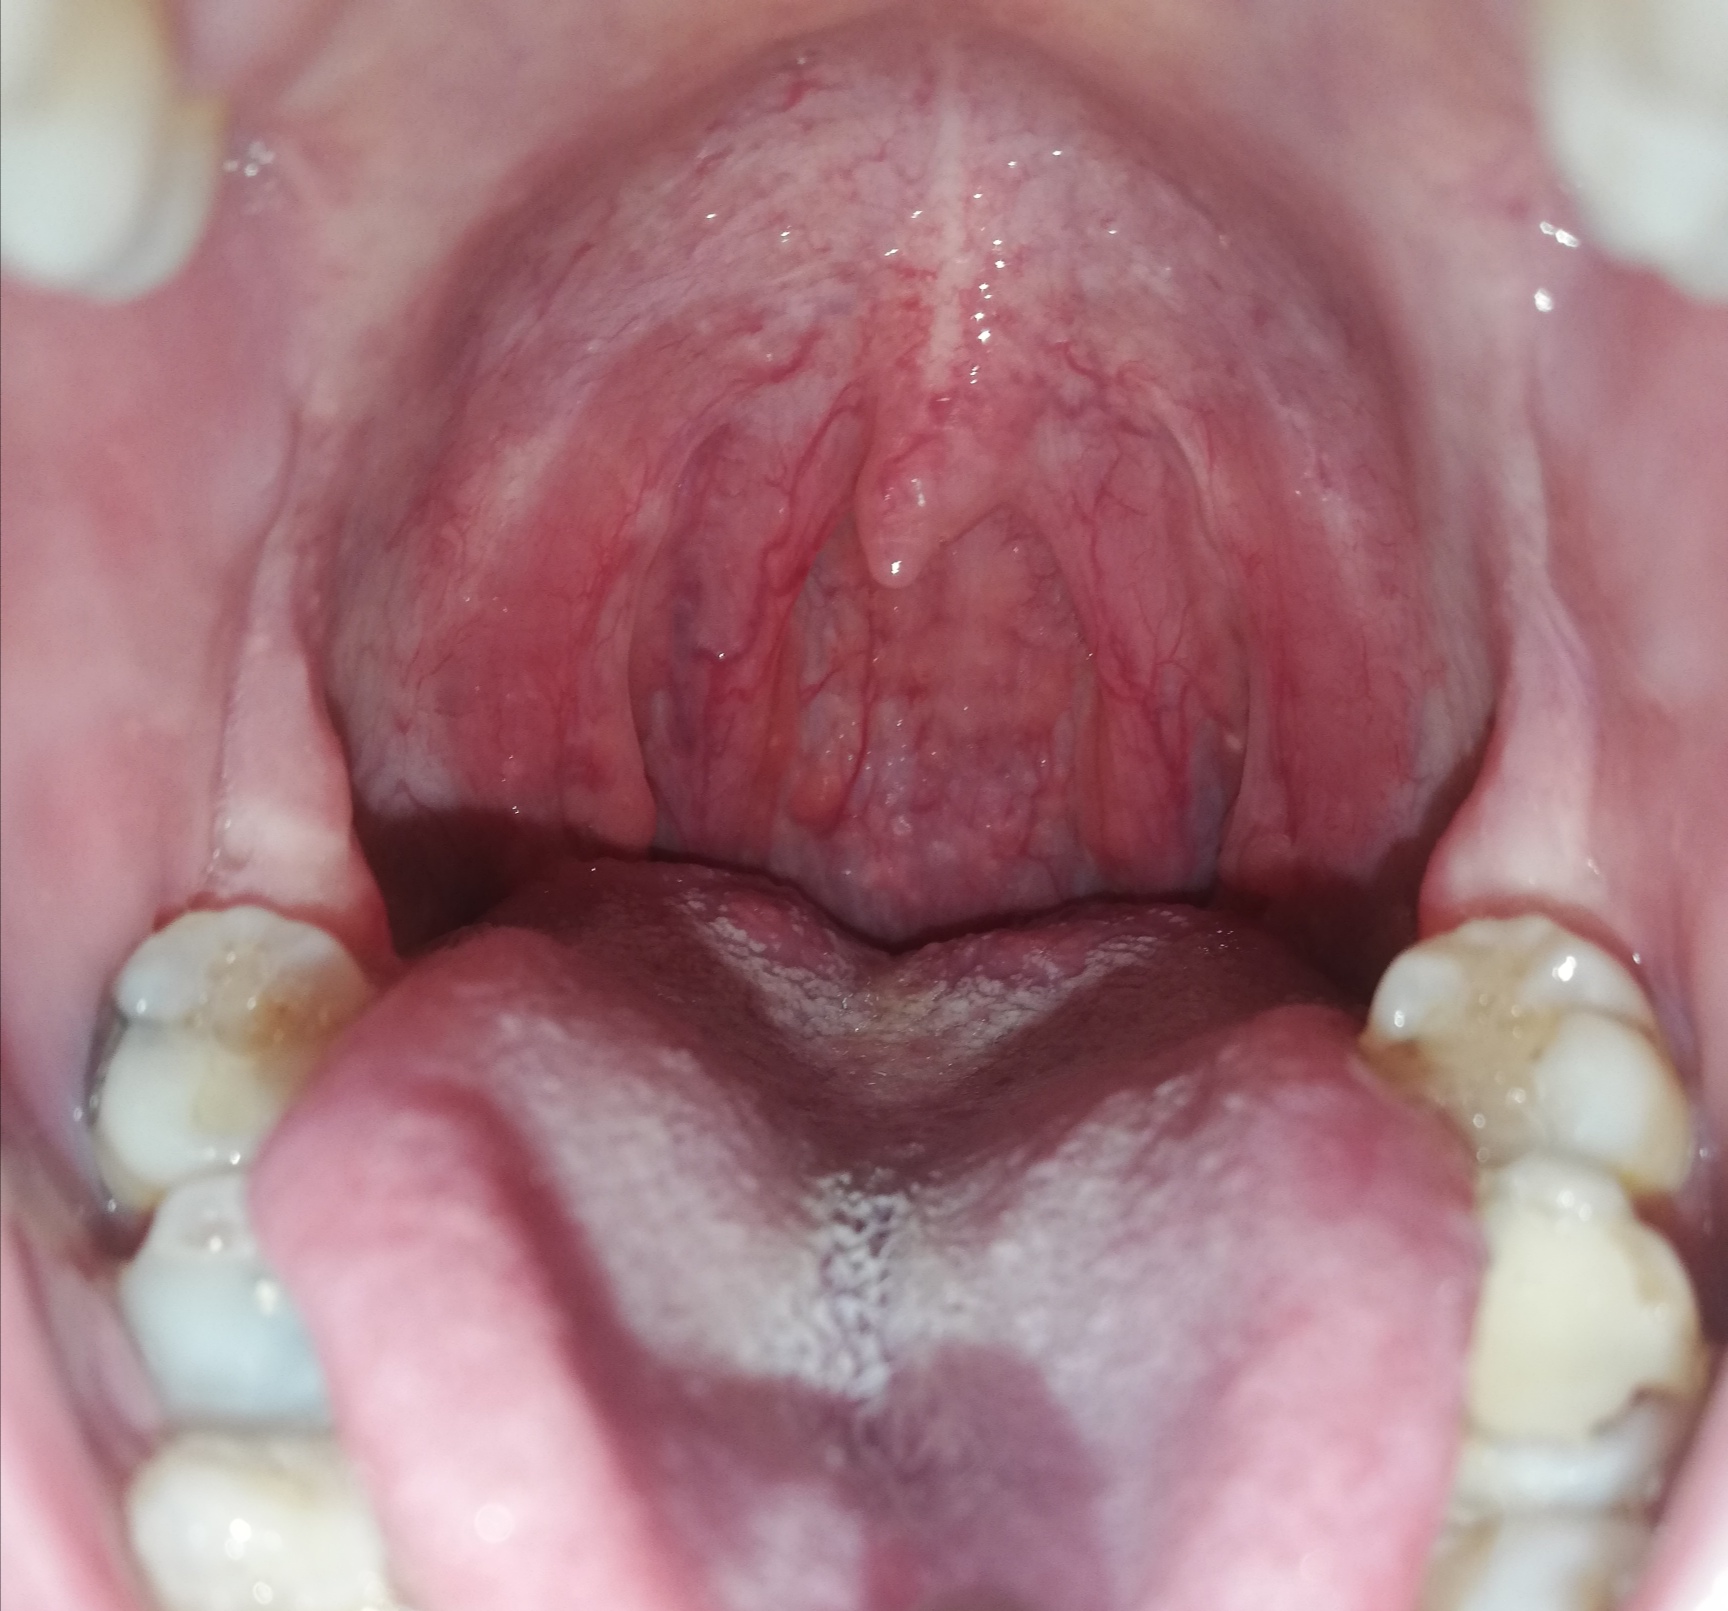

Въпреки лошата снимка и недостиг на светлина това е анатомична норма.